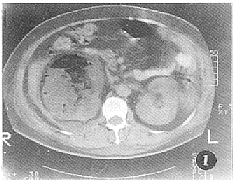

平扫示右侧肾影明显增大变形,肾实质密度不均匀,示大片状低密度积液影及点、片状更低密度积气影,可见液平,CT值分别为17 HU、-1000 HU(图1);肾脏边缘毛糙,肾筋膜增厚,肾周脂肪间隙模糊,示液体密度影填充。左肾大小、形态未见明显异常。增强检查,右肾门平面上内侧肾实质轻度强化,所扫低密度影无强化(图2)。

图2 增强扫描示右肾实质轻度强化,周围混杂密度影无强化